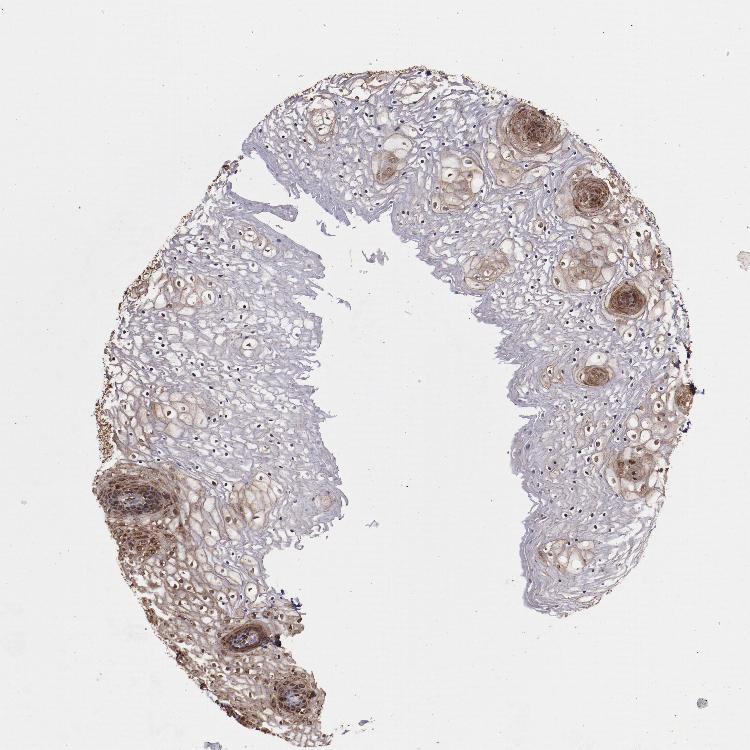

VAGINA - Antibody stainingi

Antibody staining in the annotated cell types in the current human tissue is reported as not detected, low, medium, or high, based on conventional immunohistochemistry profiling in selected tissues. This score is based on the combination of the staining intensity and fraction of stained cells.

Each image is clickable and will lead to virtual microscopy that enables deeper exploration of all samples and also displays staining intensity scores, fraction scores and subcellular localization as well as patient and tissue information for each sample.

Antibody HPA001619Antibody HPA002078

Squamous epithelial cells MediumHigh